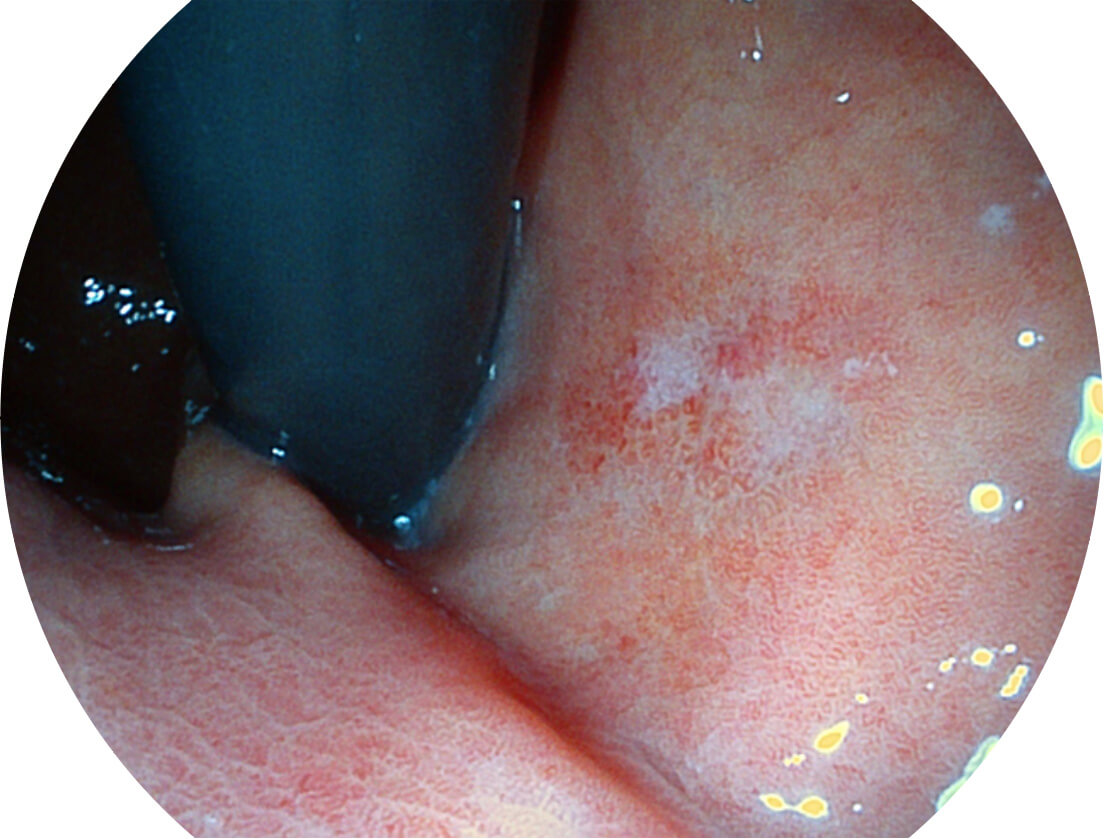

Spectral Focused lmaging, SFI

图像具有高亮度、高黏膜血管颜色对比度的特点,且不改变粘液、食物残渣、粪便的基本颜色,可在中远景下进行观察,助力消化道早期疾病的诊断。

白光图像

SFI图像

采用光路合束技术,光谱自由度高,实现了更丰富的照明模式,染色模式SFI及VIST,从远景到近景,助力消化道早期疾病诊断。